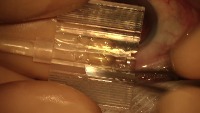

eye detetction Computer Vision Project

Classes (10)

三角刀

人工晶体定位勾

开睑器

无损伤镊

晶体植入镊

注吸器

虹膜恢复器

角膜穿刺刀

超声乳化调节杆

超声乳化针头